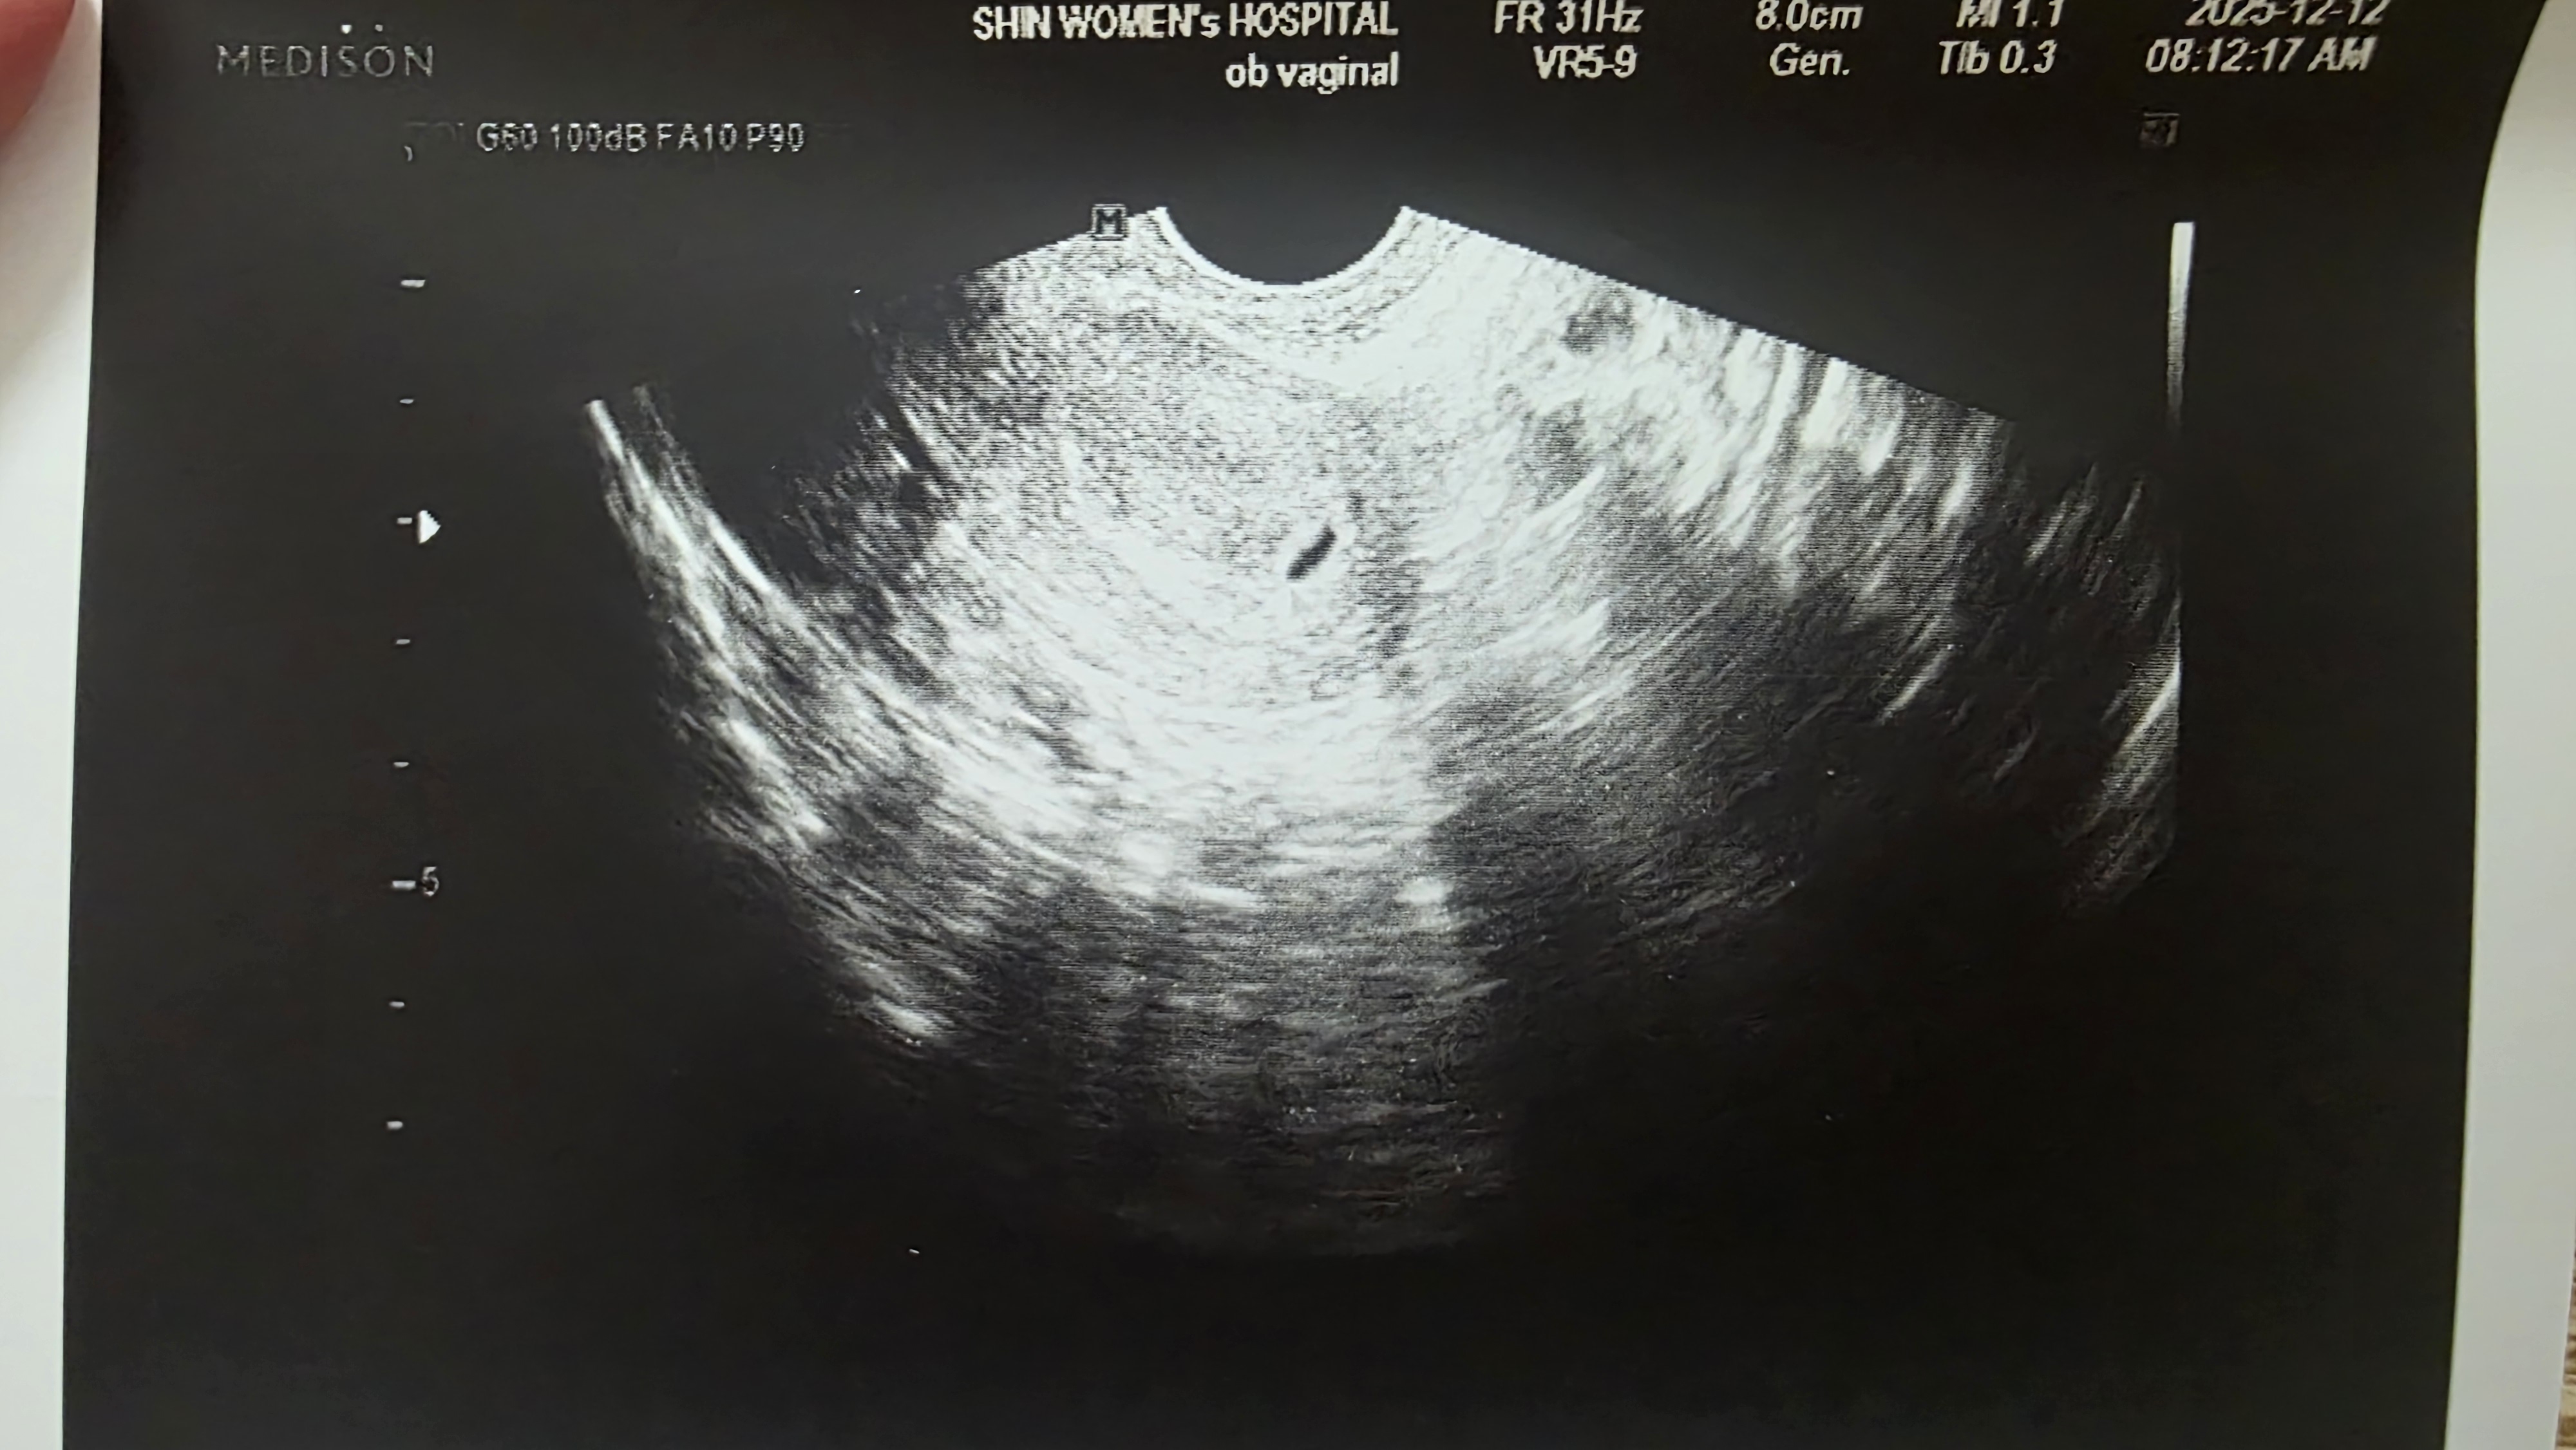

4주5일차

12월7일 생리예정일에 임테기 확인하고 바로 갓더니 수치500 이라 5일뒤에 촘파로 아기집 확인햇는데 4주3일째래요 한번 계류유산했어서 그런가... 너무 일찍 알아버린것같아요ㅜ 이번엔 심장소리 듣고싶은데 2주 어떻게 참죠? 난황보러 요번주에 가보는것도 괜찮을까요?